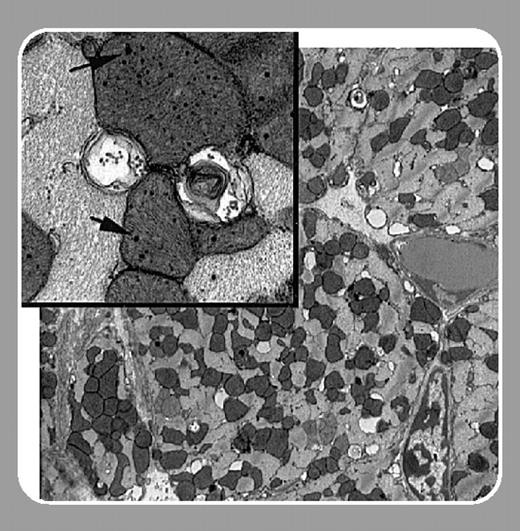

To further simulate the distribution of hemochromatosis mutations in the general population, they studied the effect of chronic administration of DOX on both heterozygous and homozygous knockout mice. Both groups of mice displayed increased mortality and excessive iron accumulation when compared with wild-type mice. Significantly, Miranda et al show that the iron accumulation results in extensive mitochondrial damage in heart tissue.FIG1